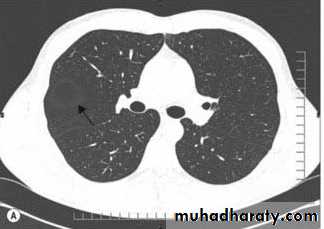

HRCT is thin section high spatial resolution CT, use for pulm. Parenchymal dis. And bronchiectasis.

bronchiectasis

5- bronchiectasis.